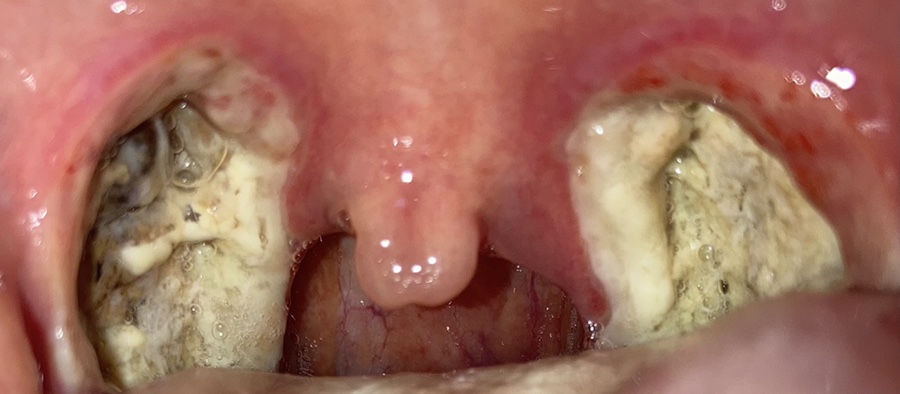

이건 수술 후 사진을 찍은 거야.

목젖이 부어 보이지 않을 정도다. 혀 뒤에 있다; 잠을 못 자고 옆으로 자야 한다. 바른 자세로 자면 숨을 쉴 수 없어 ㅋㅋㅋ 1층 내려서 의사를 만나고 목도 봐주고 출혈 등 주의사항을 말해줬고 병실에서는 약도 가루약으로 많이 받아 12시쯤 퇴원했다.

목젖은 가라앉았지만 전기로 부서졌다는데 사흘째가 되자 딱지가 심해졌다. 사진은 셋째 날과 넷째 날이 같았기 때문에 넷째 날은 찍지 않았다.